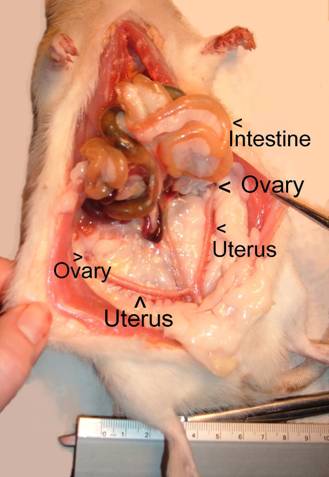

This picture shows a good view of the entire uterus

(which is shaped like a Y) and

ovaries with the other

abdominal organs pulled back out of the way.